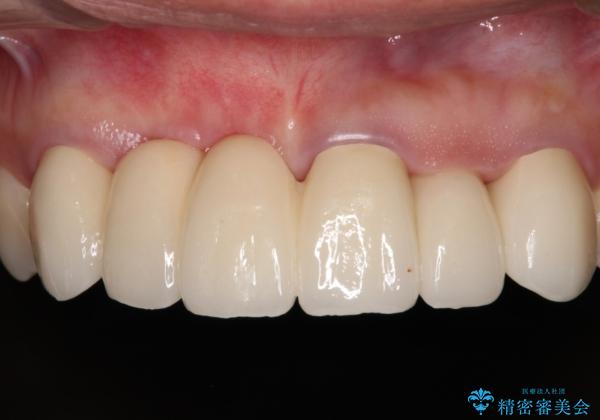

長く見える歯を治したい 歯肉移植による歯肉増大術

歯肉が痩せてしまっている状態を改善するため、口蓋から歯肉の結合組織を採取し、移植することで厚みを増大させることとし、その後オールセラミックブリッジにて補綴治療を行うこととしました。

1回の歯肉移植により歯肉の厚みは大幅に改善されましたが、折角なのでもう少し大きくしたいとの要望があり、2回目の処置も行うこととしました。

厚みも高さも十分な歯肉量を獲得することができました。